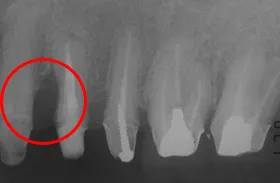

■治療前

歯周組織再生治療とは、歯周病により失われた歯周組織を再生・回復させる治療法です。

矢印の部分の歯茎が下がって、歯の根っこが見えています。